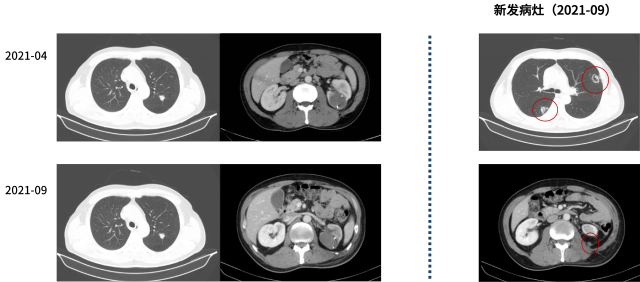

2021-09 - 2024-03

二线:帕博丽珠单抗+仑伐替尼

治疗结局:复查评效 SD

病情变化:疾病进展

2024-3-30

临床诊断

左肾透明细胞癌伴肉瘤样分化 TxN1M1 IV 期

双肺转移 纵膈、右肺门淋巴结转移 腹腔转移 右侧肾上腺转移

肌肉转移 后腹膜转移 骨转移 脑转移